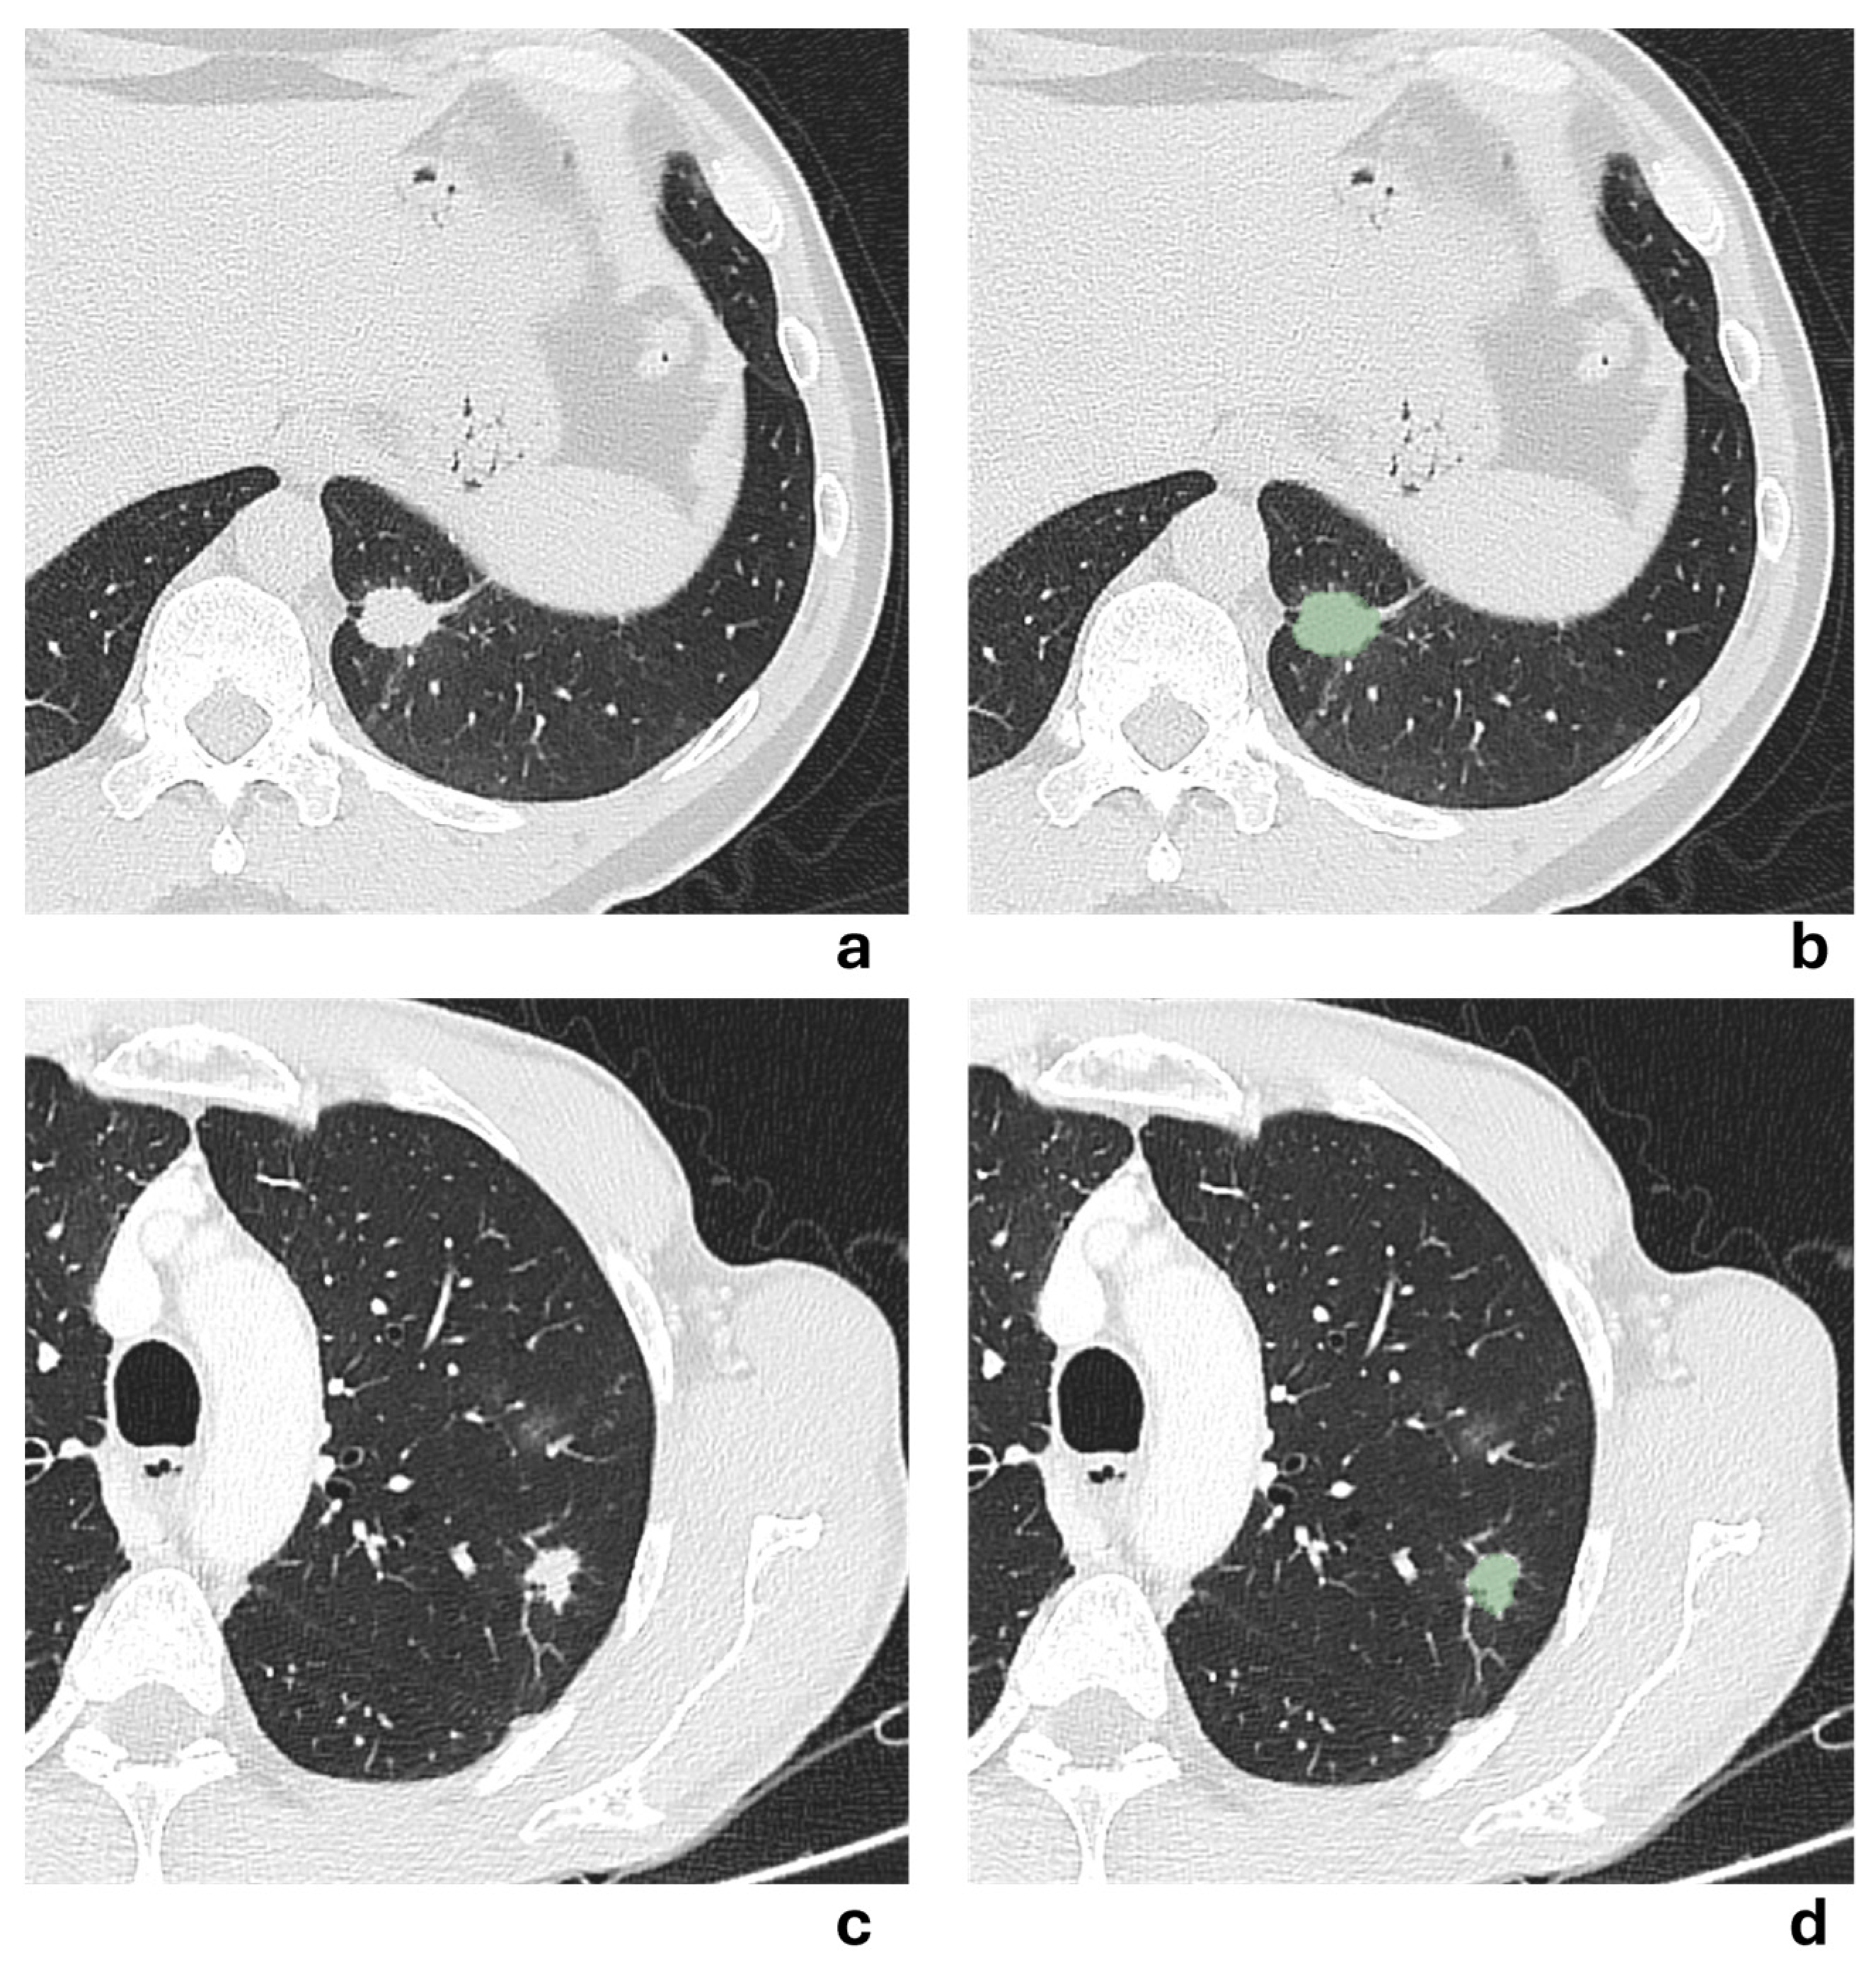

An example of a segmented lesion and the corresponding peritumoral regions is shown in Figure 1.

Two representative NSCLCS cases with a tumor major axis < 3 cm are illustrated in Figure 5. In the first case (a,b), the presence of a pleural tag suggested a radiological suspicion of pleural invasion, but it was not confirmed by histological examination. In the second case (c,d), no radiological suspicion of pleural invasion was raised due to the absence of a pleural tag, but histological examination revealed pleural invasion. All models failed to correctly predict the presence of pleural invasion, except for the 3 mm-peritumoral radiomic model.

Figure 5. (a,b) Axial chest CT scan in lung window of a 54-year-old man showing a solid irregular nodule in the anteromedial basal segment of the left lower lobe, with evidence of a pleural tag sign, measuring 14.4 mm in major axis. The corresponding segmented lesion is shown in (b). Despite radiological suspicion, histological examination revealed no pleural invasion. (c,d) Axial chest CT scan in lung window of a 65-year-old man showing a solid irregular nodule in the apical segment of the left lower lobe, without evidence of pleural tag sign, measuring 22.3 mm in major axis. The corresponding segmented lesion is shown in (d). Histological examination revealed pleural invasion, despite no radiological evidence being suspected.